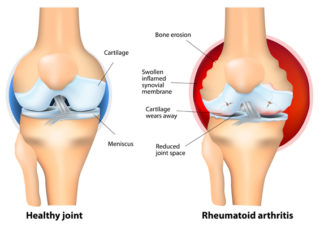

To understand how RA affects your body, it’s helpful to know a little about your joints.

Joints are places where bones meet. Bones, muscles, ligaments and tendons work together so you can twist, bend and move about.

The ends of your bones are covered in a thin layer of cartilage. It acts like a slippery cushion absorbing shock and helping your joint move smoothly.

The joint is wrapped inside a tough capsule filled with synovial fluid. This fluid lubricates and nourishes the cartilage and other structures in the joint.

When you have RA, and the immune system targets your joints, it causes a build-up of synovial fluid and inflammation of the tissues that line the joint (synovial membrane). This causes pain, heat and swelling.

Cartilage becomes brittle and breaks down. Because the cartilage no longer has a smooth surface, the joint becomes stiff and painful.

Ligaments, tendons and muscles surrounding the joint can also be affected, causing joints to become unstable.